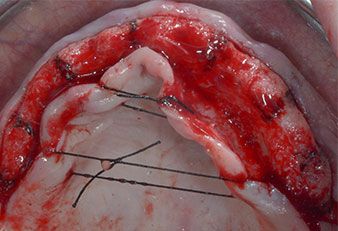

Due to the relatively hard bone (D2) in this area, the 10 mm long implant sites at positions 11 and 21 were finalized with a 4 mm diameter rotary drill, in combination with a W&H WS-75 L surgical contra-angle handpiece, the W&H Implantmed implant motor and the optional W&H Osstell ISQ module. In contrast, due to the soft bone the posterior sites were prepared to a final 3 mm diameter using the Piezomed I3P instrument. The implants were finally placed transgingivally to osseointegrate for three months (Figs. 6-10). The existing denture was retained on four provisional implants (Fig. 8).

10-mm tissue level implant

Fig. 6: A 10-mm tissue level implant is placed at position 21. The implant at position 11 and the three left posterior 4-mm implants are already in place.

Provisional implants

Fig. 8: After fixation of the gingiva formers provisional implants are placed at positions 18, 12, 22 and 28.